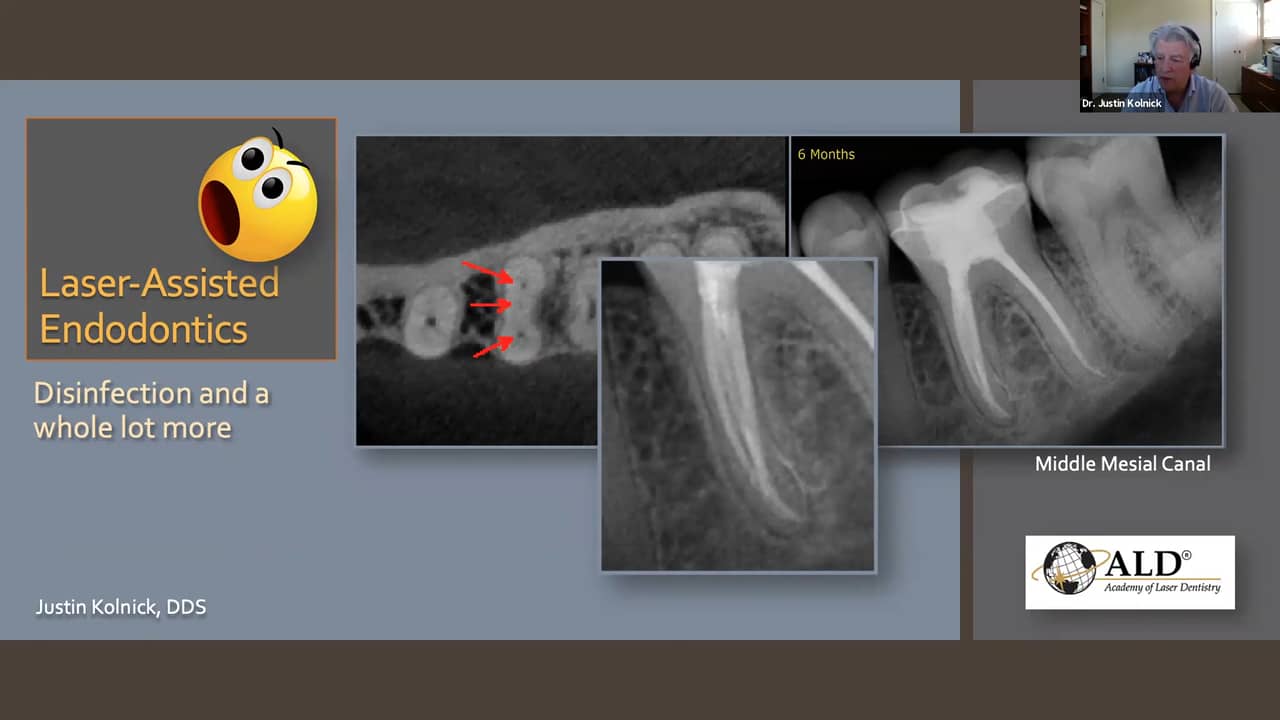

From vimeo.com

LaserAssisted Endodontics Disinfection and a Whole Lot More on Vimeo Laser Endodontic Disinfection The efficacy of laser therapy applications in root canal disinfection with or without various irrigants protocols remains. Root canal treatment is the most effective and widely used method for controlling infection, promoting periapical healing, and. Laser energy, when added to root canal procedures, presents advantages and disadvantages. Laboratory studies in extracted teeth suggest that, with regard to canal disinfection, lai. Laser Endodontic Disinfection.